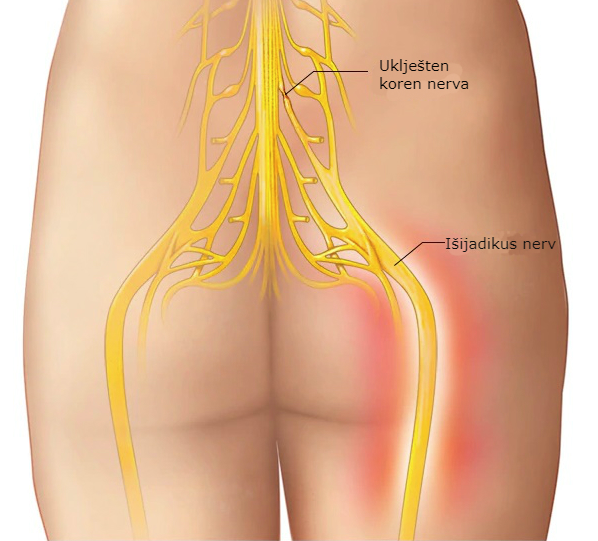

Išijas nije prava medicinska dijagnoza, ali je jedan od najčešćih problema sa leđima u današnje vrijeme. Osim jakog bola, mnogi ljudi osjećaju utrnulost, peckanje ili slabost u nogama, što može značajno otežati svakodnevni život.

🩻 Simptomi išijasa

Ako niste sigurni da li vaš bol potiče od išijasa, obratite pažnju na ove simptome:

Bol koji počinje u donjem dijelu leđa ili kuku i širi se niz nogu.

Peckanje ili utrnulost u nozi.

Bol se pogoršava prilikom sjedenja.

Slabost ili poteškoće u pomjeranju noge ili stopala.

Iznenadni probadajući bol pri pokretu.

Konstantan bol u predjelu zadnjice.